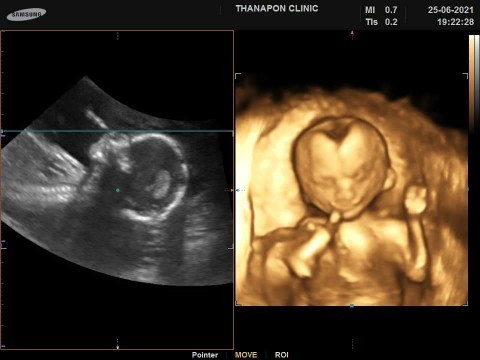

ซาวด์ตอน 28w 4d ตอนนี้ 30w แล้วค่ะ🥰